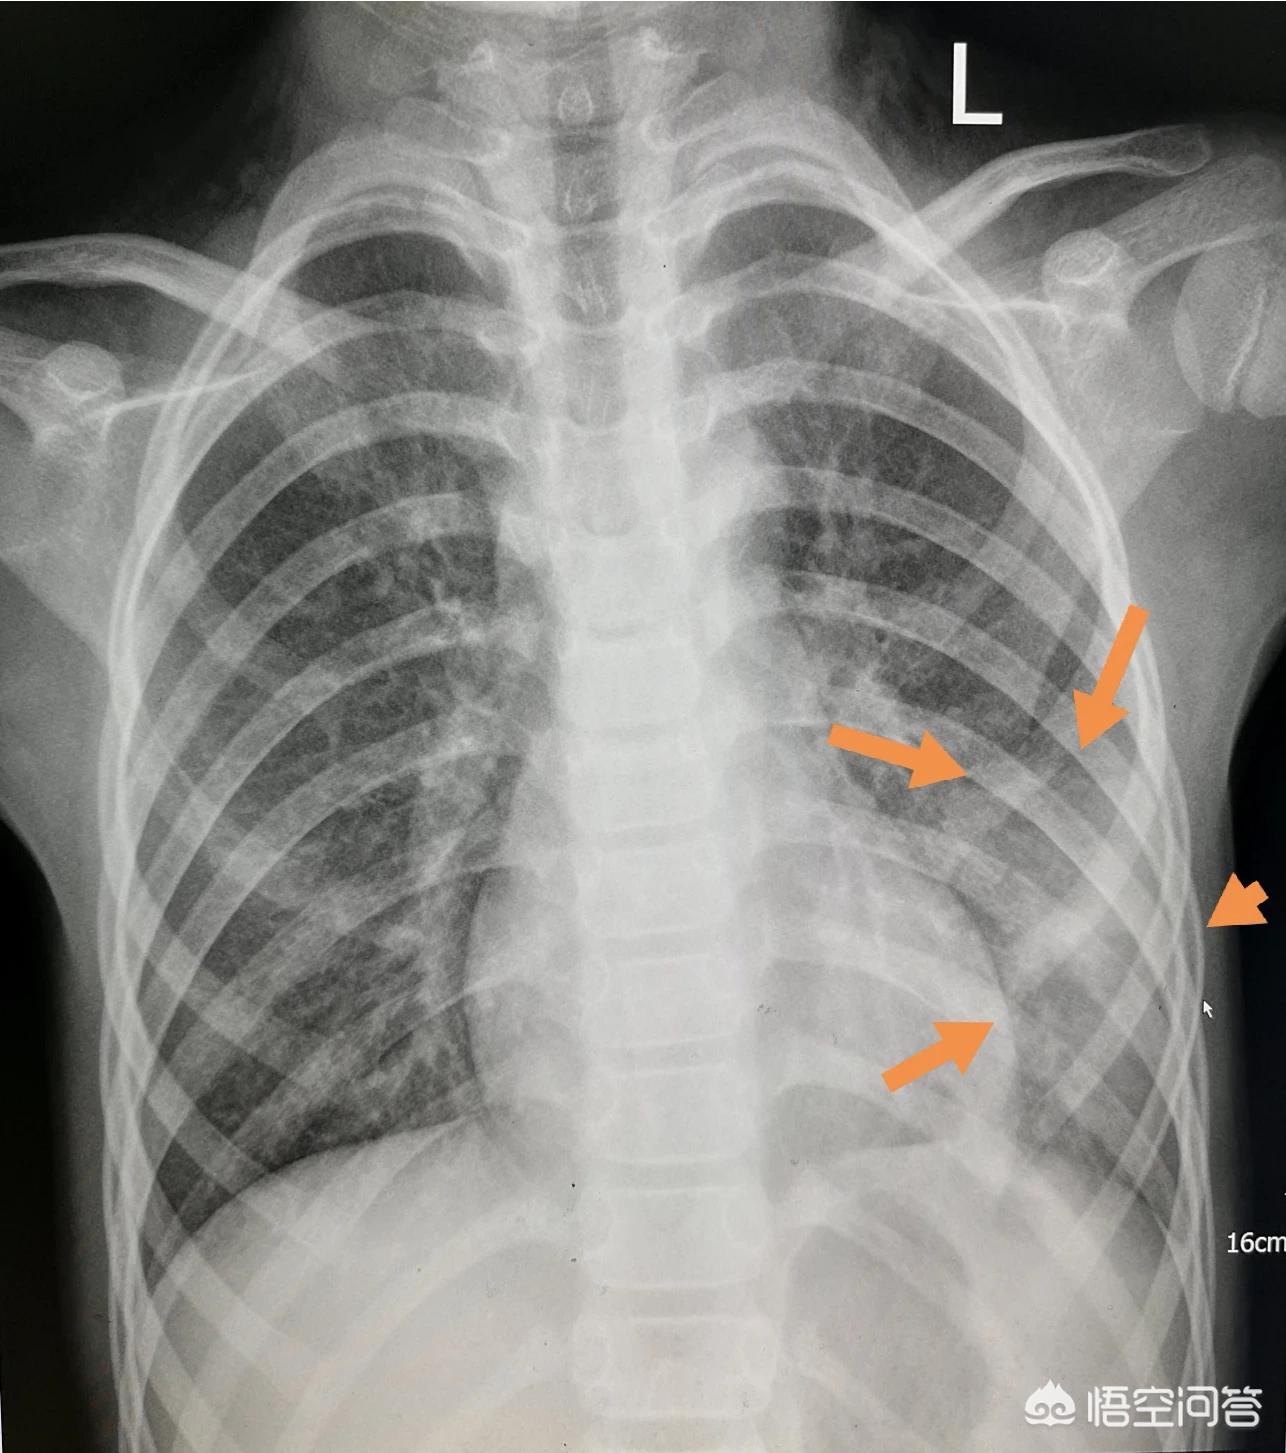

这位2岁小朋友咳嗽一周,发热三天,胸部拍片显示双侧肺炎,右侧面积很大,需要紧急住院治疗。